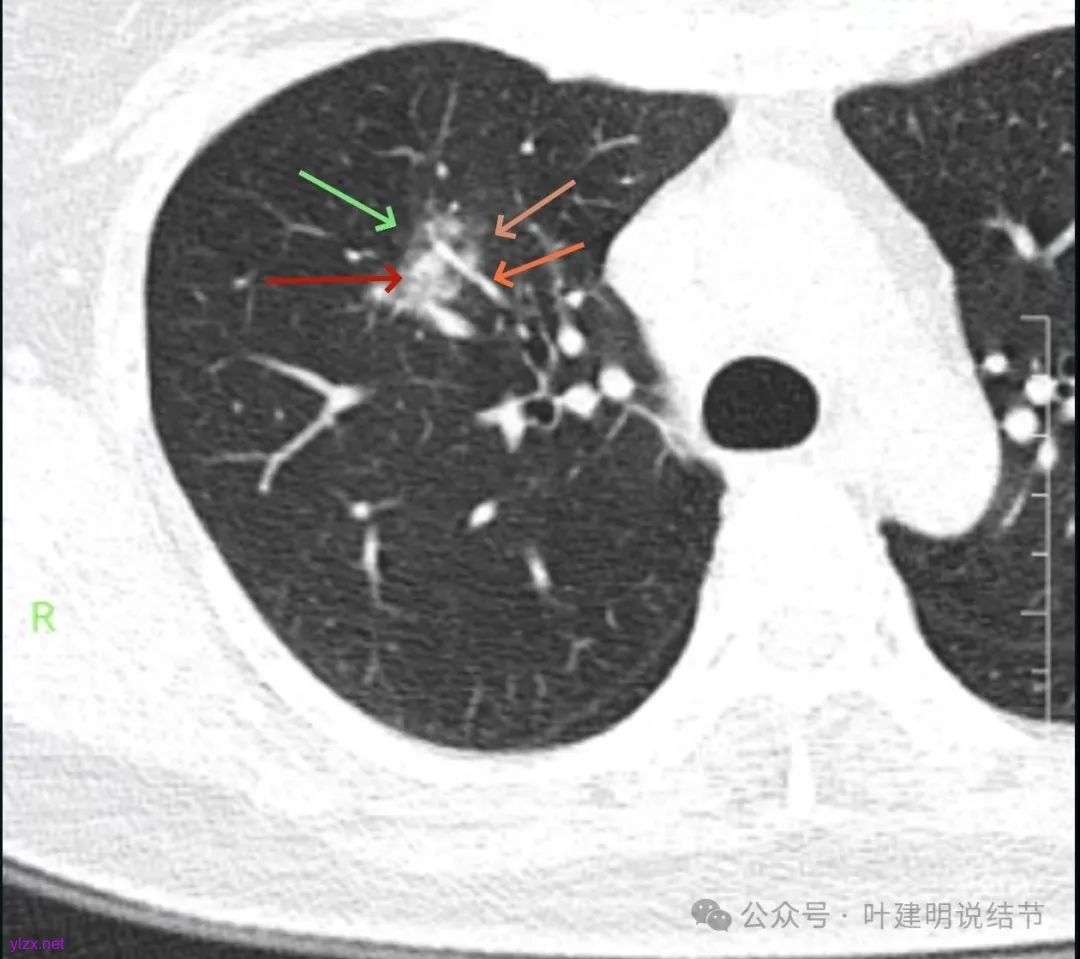

影像展示与分析:

你的右上叶这个病灶基本上肯定是肺癌,要尽快处理。从影像上看有以下特点:1、整体轮廓清楚,不似普通炎症的周围有晕或阻塞性改变;2、边缘明显的浅分叶,总体上的感觉膨胀性明显,不管哪个层面看上去都是鼓鼓的;3、边缘区域有磨玻璃成分而且也是分叶状的;4、部分层面见血管进入;5、空腔病灶的壁厚薄不均,内壁不光滑。我考虑中低分化肺癌,由于腔静脉旁有明显肿大淋巴结,需要进一步完善增强CT以及PET-CT检查以明确有无远处转移,是否仍可手术治疗(从病灶本身来说是可以肺叶切除治疗的)。要尽快处理。意见供参考!